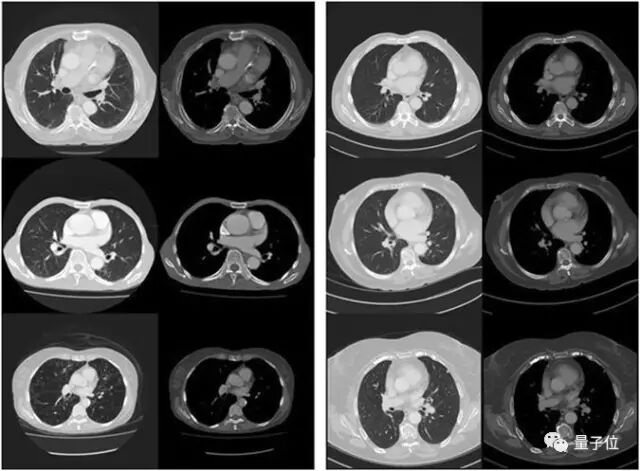

本文来自AI新媒体量子位(QbitAI) 只需要简单查看器官图片,人工智能就可以预测患者的剩余的生命长度,这是澳大利亚阿德莱德大学的最新研究成果。 这一成果发表在最新的《自然》杂志旗下《科学报告》中,被认为将对严重疾病的早期诊断和医疗干预产生影响。 阿德莱德大学公共卫生以及计算机两个学院的研究人员,使用人工智能技术分析了48例患者的胸部医学影像资料,然后预测哪些患者有可能在五年内死亡,准确率达到69%,这与临床医生的“手动”预测不相上下。 “预测患者未来的生命周期的价值在于,可以让医生对不同患者展开更有针对性的治疗”,阿德莱德公共健康学院的放射科医师和博士生Luke Oakden-Rayner表示。 生物学年龄的准确评估和患者寿命的预测,一直受制于医生无法测量每个器官的健康状况。而阿德莱德大学的最新研究,使用了深度学习技术对医学影像进行理解